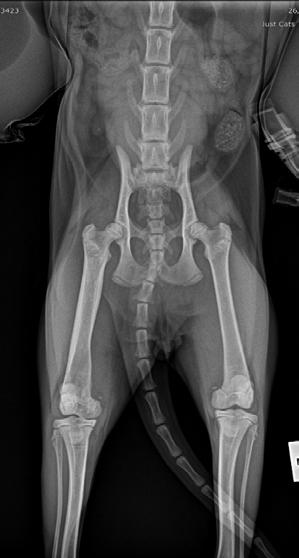

Hotch was booked in for routine castration 4 weeks later with repeat radiographs taken, which already showed improvement (see images). He continued with only oral clindamycin for a further 4 months with regular weight checkups, and dose adjustments as required. We did repeat radiographs under mild sedation a further 2 times to ensure the bone was remodeling as expected (Figure 3 ). Hotch responded almost immediately to the antibiotics and never showed signs of lameness or pain again. He was a robust, busy kitten.

Final radiographs were taken 2 months later in January of this year. There were only mild boney changes present now and it was decided that Hotch as a rescue cat could be re-homed to a forever home.

2

3 4A 4B 4C

Figure 3. Radiograph of the affected leg showing resolving infection and remodeling of the lesion back into a more normal skeletal appearance

Figure 4. Final radiographs showing near normal appearance of the lesion (A & B) after extensive remodelling during growth. C is the contralateral normal limb for purposes of comparison.